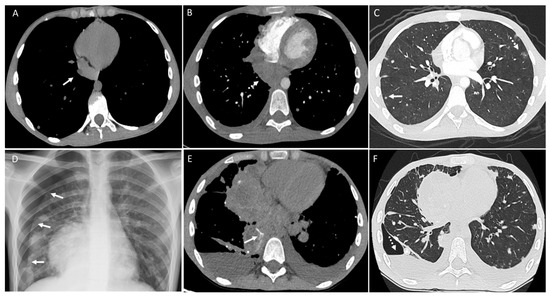

3. Pleura

4. Mediastinum and Hilum

5. Cardiac and Major Thoracic Vessels